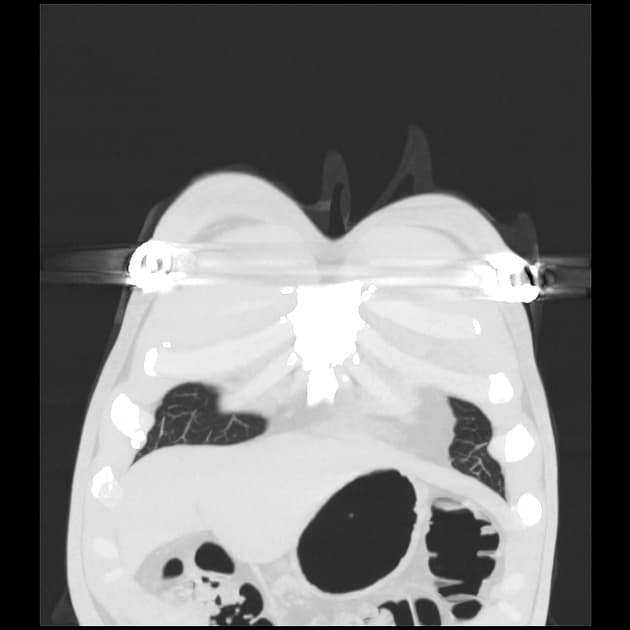

Series (2)

Lateral

- Có các vùng mờ đậm không đồng đều dạng khoảng khí (patchy airspace opacities) và dày lên kẽ (interstitial thickening) lan tỏa ở cả hai phổi.

- Không thấy tràn dịch màng phổi (pleural effusion) hay hạch trung thất (lymphadenopathy).

- Tim không giãn, các cấu trúc trung thất ở vị trí bình thường.

- Xương lồng ngực không thấy tổn thương tiêu xương hay gãy.

Viêm phổi nguyên phát dạng không điển hình (Primary atypical pneumonia)